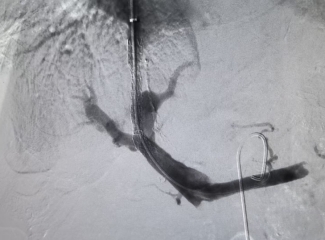

“肚子明显缩小了,腹胀的问题也得到了解决,食欲也有所改善。这是我这一年多以来最舒服的时候了,感谢医生!”近日,65岁王某的肝硬化顽固性腹水、门脉高压终于得到缓解,结束了一年来的病痛折磨。 来自湖南的王某(化名)因乙肝多年导致肝硬化伴顽固性腹水,患者腹部膨隆,形似足球,腹胀难忍,行动受限,当地医生在通过常规利尿、补充白蛋白、腹腔穿刺抽水等治疗方法,也只能暂时缓解症状,大约半个月后,又出现腹水。在这一年的时间内,王某因反复腹水住院5次,生活质量严重下降。他和家人慕名来到陆军军医大学新桥医院消化内科,科室介入手术团队多次会诊,最后为其实施了经颈静脉肝内门体分流术(TIPS),很快缓解病症。 “TIPS手术目前已广泛应用于药物治疗无效的门静脉高压及其并发症。作为微创手术,TIPS手术具有创伤小、住院时间短、患者恢复快的优点,且风险及术后并发症较传统外科手术明显降低。”据新桥医院消化内科徐征国副教授介绍,TIPS手术在我国已有近三十余年的发展,技术相对成熟。急性食管胃静脉曲张出血、门静脉高压性胃病、难治性或复发性腹水等多种疾病都可以接受TIPS治疗。 据悉,TIPS手术是在肝内开通门静脉与肝静脉之间的通道,并放置支架支撑,从而建立血管桥连接两大静脉系统通路,分流门静脉血流,达到降低门静脉高压的目的。手术通过颈部的一个小穿刺口进行,创伤小、住院时间短、患者恢复快。由于是微创手术,风险及术后并发症较传统外科手术明显降低。需要注意的是,TIPS手术是一项综合性手术,对医生能力提出了极高的要求。医生必须具备丰富的介入手术经验,也需要精通穿刺、影像识别、球囊扩张、支架植入等高精技术。 TIPS手术,是介入手术的“天花板”,需要精准的判断、精细的操作。新桥医院消化内科从2013年开展TIPS手术,TIPS技术已发展成熟。科室有徐征国教授、赵泳冰教授、周昊医师等介入专家,配备先进血管造影系统(DSA)设备,目前每年TIPS手术量超200台,经验丰富。